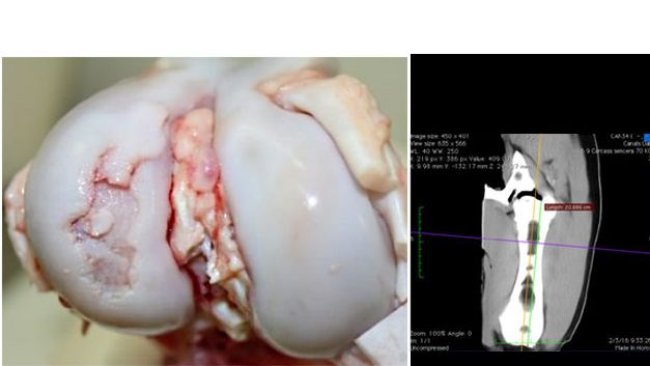

Questo articolo esamina l'effetto dei componenti delle diete sull'osso e sull'osteocondrosi, la principale causa delle zoppie e la causa dell'eliminazione delle giovani riproduttrici. Pertanto, concetti importanti da considerare nelle diete per l'allevamento delle scrofette.